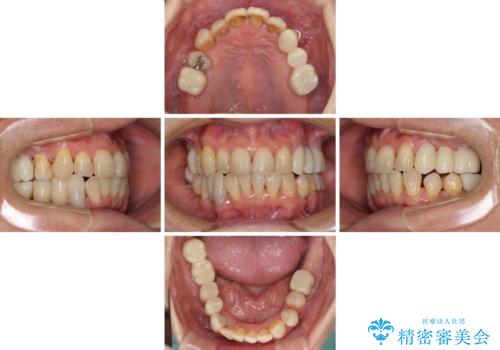

歯並びや奥歯の痛み 色々と治したい 総合歯科診療

- 歯並びやグラグラする奥歯など、気になる所を全部治したいとのことで来院された患者様です。

奥歯は咬み合わせや歯周病により歯槽骨が失われていたり、むし歯や破折している歯などがあったりと、歯周病治療やインプラント補綴、矯正治療など、総合的に治療が必要と診断されました。

まずは歯周病治療やインプラント埋入を行い、環境が整った後にワイヤーを併用したインビザライン矯正を行い、オールセラミッククラウンにて補綴治療を行うこととしました。

初診時に4年かかりますとお伝えし、実際に4年数ヶ月を要する治療となりました。

治療中は仮歯が頻繁に脱落したり、歯周外科によりむき出しとなった歯根が知覚過敏を起こしたりと、苦労は絶えませんでしたが、4年の治療の後にスッキリと仕上げることができました。